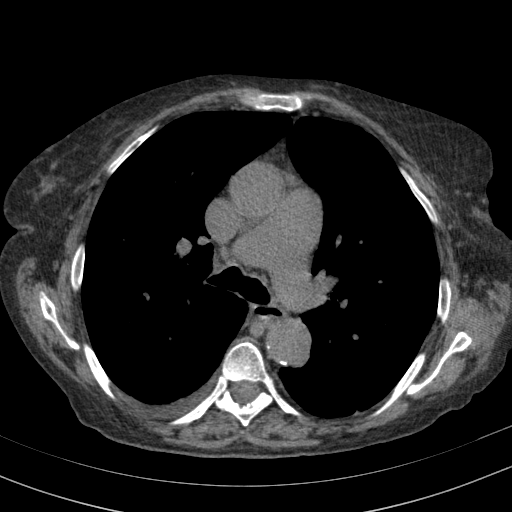

Reconstructed NATIVE CT scan (cycle consistency)

Full window (WL 1023.5, WW 4095 β†’ Low βˆ’1024, High +3071)

Actual HU range: [-1024.0, 609.2]